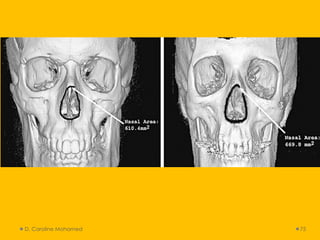

• Anatomical features:

• Sinus configuration: maxillary and frontal

• Anatomical features: •Sinus configuration: maxillary and frontal • Anterior nasal spine • Mandibular canal • Condylar and coronoid process • TMJ • Skull sutures • Soft tissues features: rugae (rugoscopy) and lip (cheiloscospy) prints. • Other D. Caroline Mohamed 39